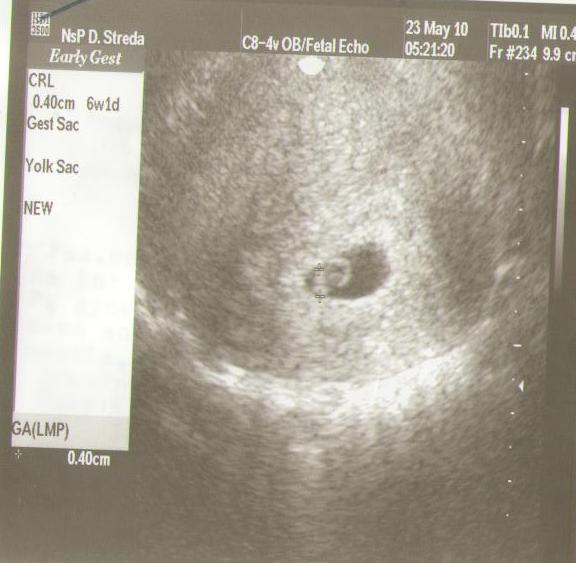

Dnes som bola na tom NT a všetko vyzerá v norme ,ešte to porovnajú s odberom krvi a potom to budem vedieť presne ...drobček rastie ,srdiečko bije ,hýbe sa jedna radosť ,tak sa teším ! 🙂